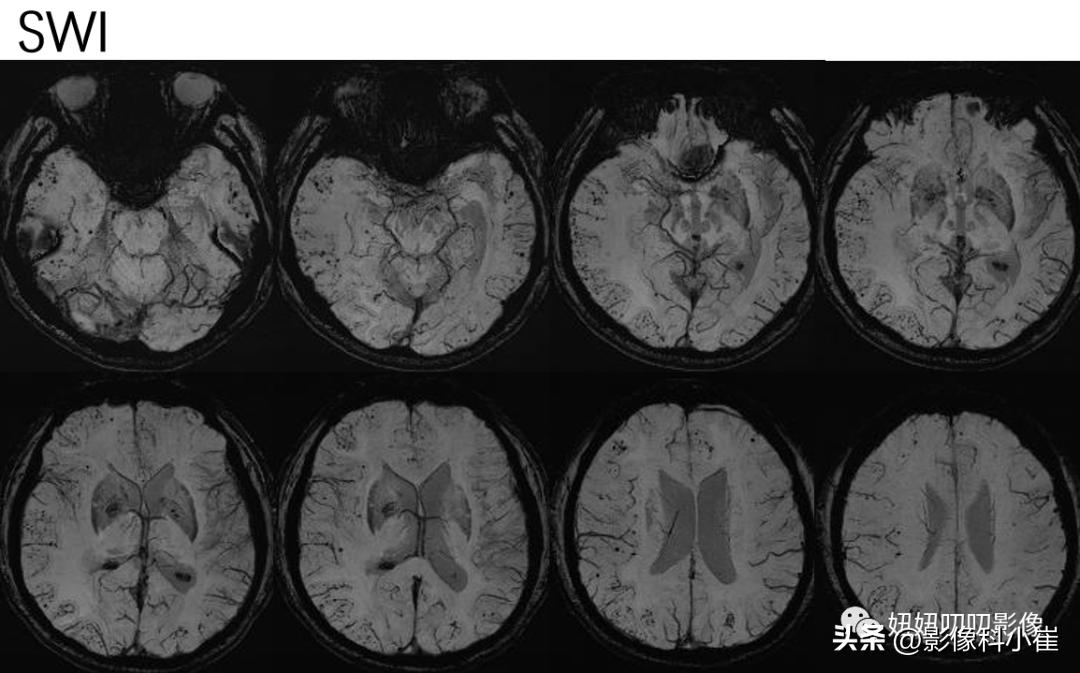

SWI:双侧小脑半球、大脑半球见多发大小不等斑点状低信号,病变多位于皮质区及皮髓质交界区。

SWI:双侧大脑半球表面见多发、弥漫性低信号灶。